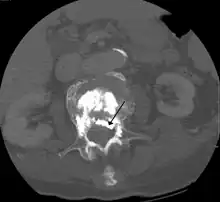

During the procedure, bone cement is injected with a biopsy needle into the collapsed or fractured vertebra. The needle is placed with fluoroscopic x-ray guidance. The cement (most commonly poly methyl methacrylate (PMMA), although more modern cements are used as well) quickly hardens and forms a support structure within the vertebra that provide stabilization and strength. The needle makes a small puncture in the patient's skin that is easily covered with a small bandage after the procedure.[2]

Some of the associated risks are from the leak of acrylic cement to outside of the vertebral body. Although severe complications are extremely rare, infection, bleeding, numbness, tingling, headache, and paralysis may ensue because of misplacement of the needle or cement. This particular risk is decreased by the use of X-ray or other radiological imaging to ensure proper placement of the cement.[2] In those who have fractures due to cancer, the risk of serious adverse events appears to be greater at 2%.[23]